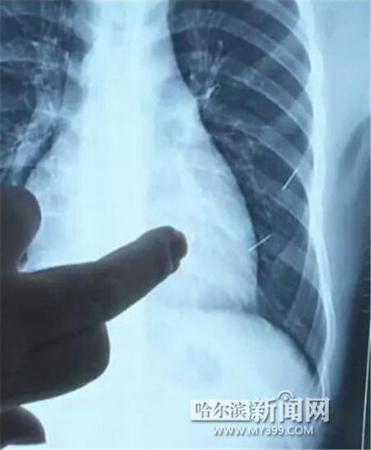

醫(yī)生指出X光片上的針狀物

昨日上午,記者在哈醫(yī)大二院第八住院部心外三病房找到了躺在病床上痛苦不堪的董立仁,家屬正在他身旁不斷安慰著他。見記者前來,董立仁母親李百燕拿出一張X光片,上面可以清晰地看到胸腔內(nèi)一共有4根針狀物,其中一根在心臟部位,兩根在胸腔壁上,還有一根在腹腔壁上。

昨天16時30分左右取針手術開始。因鋼針隨時會危及患者生命,此次手術定義為大型手術。開胸后,醫(yī)生打開董立仁心包,發(fā)現(xiàn)一枚鋼針已深深扎入心臟,僅露出1厘米長度在外。拔出鋼針后,醫(yī)生發(fā)現(xiàn),這枚針長達5厘米。受鋼針影響,心包出現(xiàn)大量積液,近800毫升。

隨后,在下胸壁位置,第二枚鋼針順利取出。在尋找另兩枚鋼針過程中,普外、胸外多名醫(yī)生也參與手術,為主刀醫(yī)生提供更為穩(wěn)妥的處理建議。根據(jù)X光片顯示位置,醫(yī)生未在患者體內(nèi)找到剩余兩枚鋼針。醫(yī)生懷疑,其中一枚鋼針可能深藏在肋骨骨膜位置,無法尋找,最后決定結束手術,做進一步觀察,研究下一次手術方案。